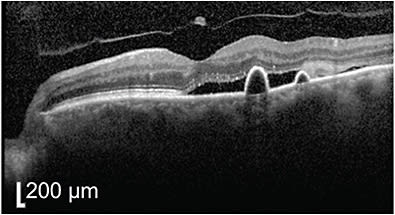

At 1 month, sub-photoreceptor excrescences began to appear (Figure 3), which is, in my experience, a poor prognostic factor for visual outcomes following resolution. The vision had decreased slightly to 20/25, and the patient was notably anxious about the worsening vision and fluid. PDT was performed to an area of 1700 µm with 15 mg of verteporfin. At 6-week follow-up, the patient described complete resolution of his metamorphopsia left eye but his vision remained at 20/25. Drusenoid changes persisted subfoveally (Figure 4).